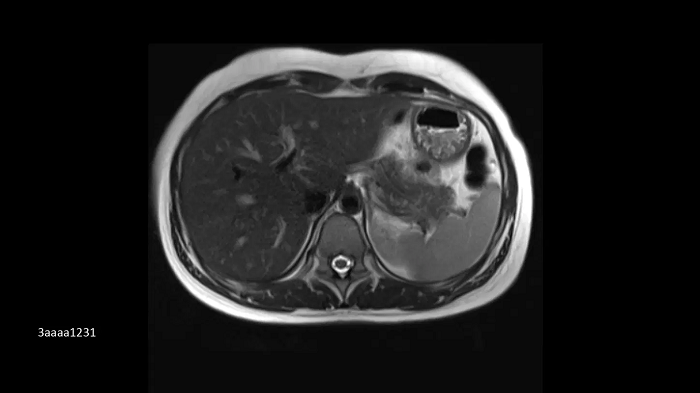

Compressed Sensing GRASP-VIBE

GRASP-VIBE Compressed Sensing for dynamic liver imaging in free-breathing patients who cannot hold their breath reliably.

- BioMatrix Spine 72

- Body 18

Image Credit: University Hospital Tübingen, Germany